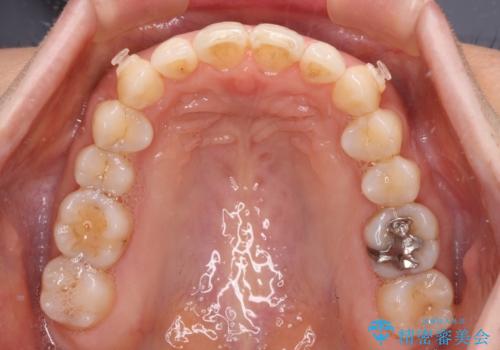

インビザライン・ライトは提供されるマウスピースの数に制限があり、通常のタイプよりもマウスピース提供期間が短くなっている一方、安価に治療を行うことができるプランです。

治療のゴールも変更できないため、軽微な歯列不正や、後戻り改善などに適しています。